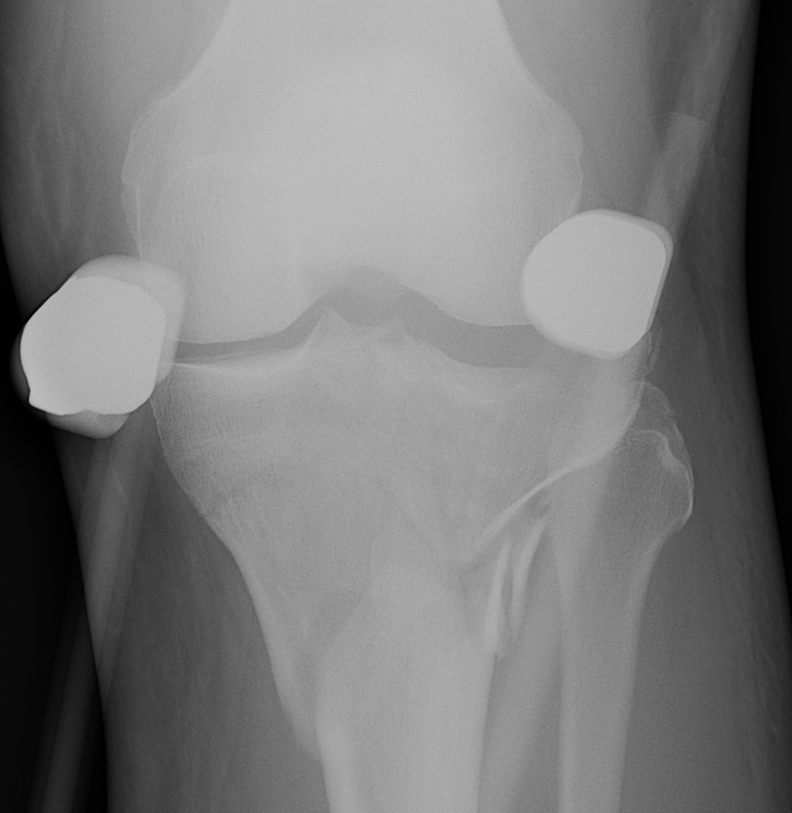

II. Lateral Split Depression

- often seen in young patients with high energy injuries

- vary in severity